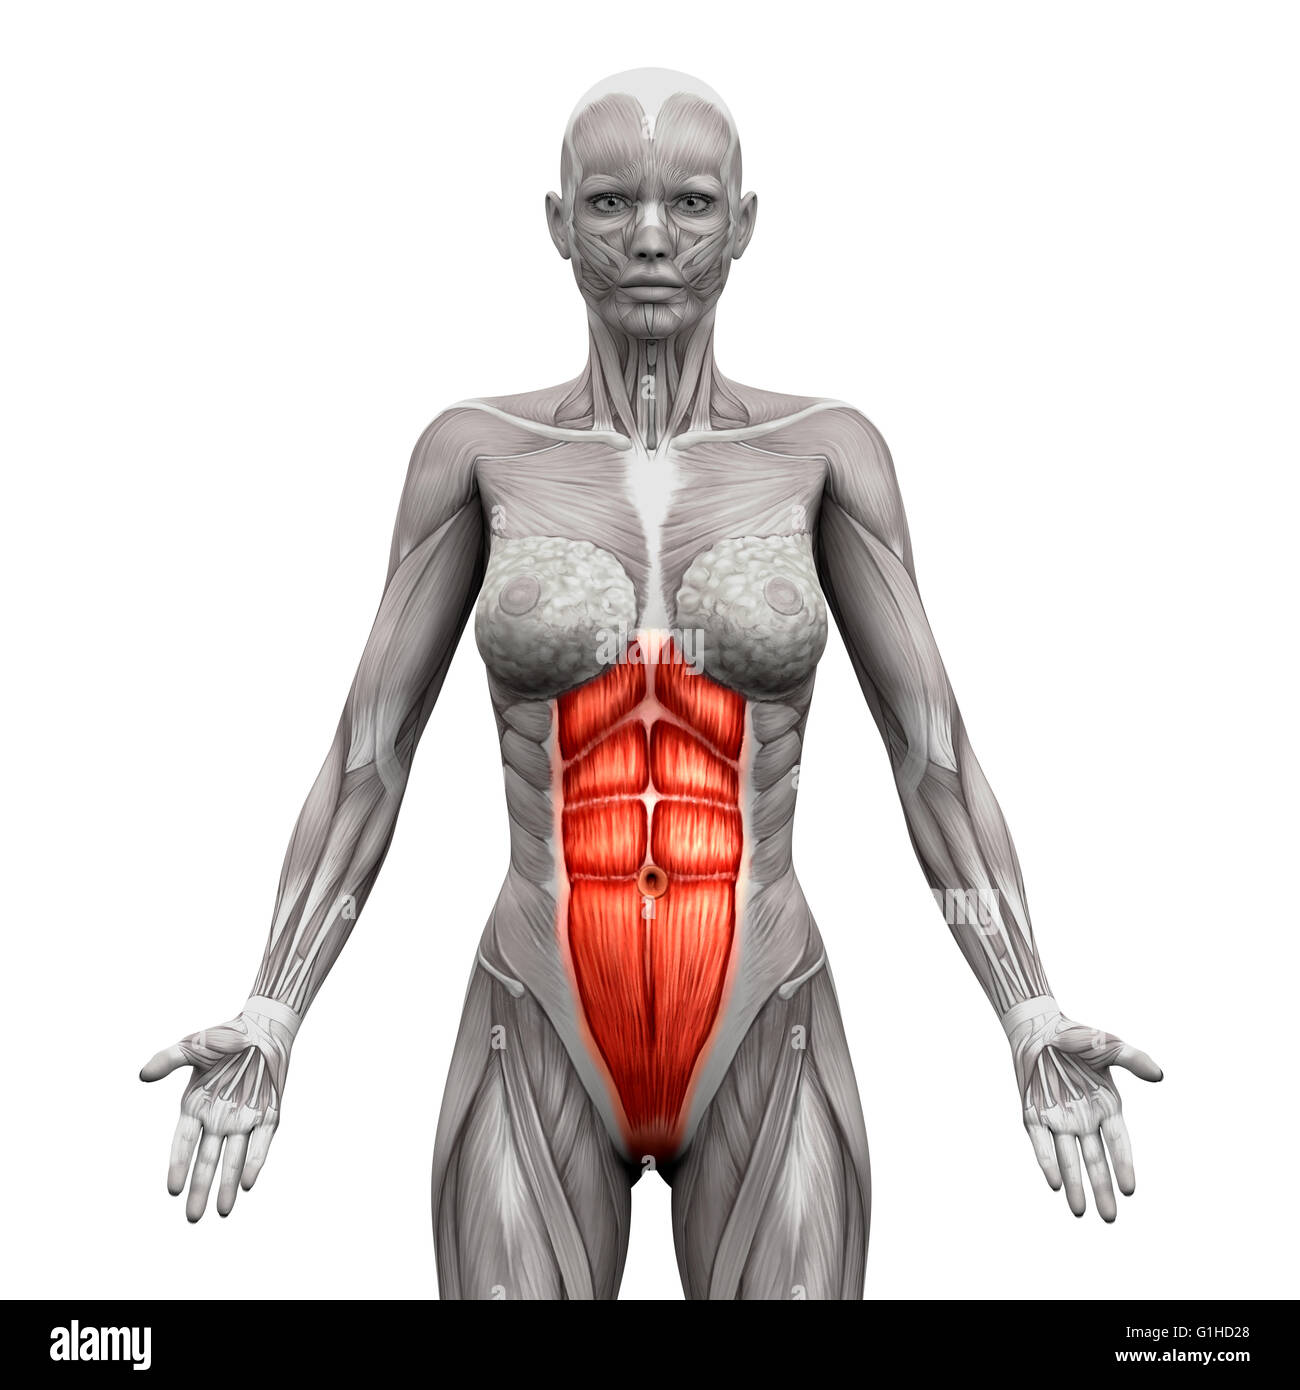

- Grand Droit Abdominal Muscles Anatomie - isolé sur blanc - 3D illustration Banque D'Imageshttps://www.alamyimages.fr/image-license-details/?v=1https://www.alamyimages.fr/photo-image-grand-droit-abdominal-muscles-anatomie-isole-sur-blanc-3d-illustration-104260304.html

- Grand Droit Abdominal Muscles Anatomie - isolé sur blanc - 3D illustration Banque D'Imageshttps://www.alamyimages.fr/image-license-details/?v=1https://www.alamyimages.fr/photo-image-grand-droit-abdominal-muscles-anatomie-isole-sur-blanc-3d-illustration-104260304.htmlRFG1HD28–- Grand Droit Abdominal Muscles Anatomie - isolé sur blanc - 3D illustration